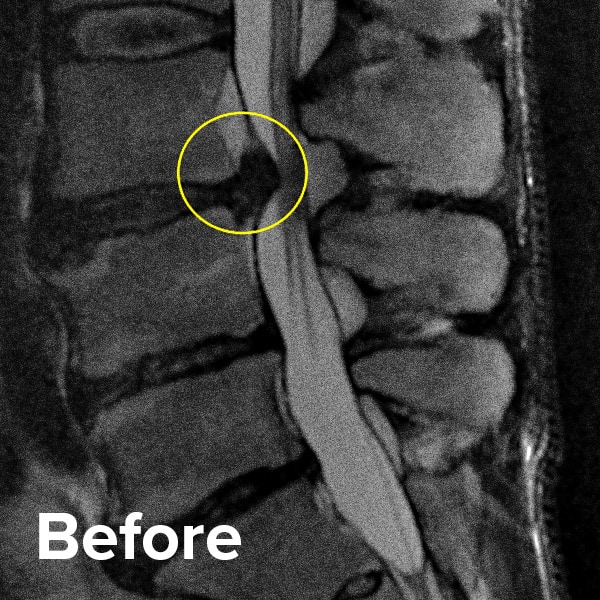

Herniated Disc MRI

Below are MRI images of the outcome of a patient who had a Regenexx PL-Disc procedure to treat a subligamentous disc herniation. After the procedure, their pain dropped quickly, and they returned to their normal activities within weeks.

Scroll the arrow to the right to see the MRI of the disc before the Regenexx PL-Disc procedure — the white/lighter area indicates damage. Scroll to the left to see the MRI of the disc after. The images are two years apart from the original treatment date.

Herniated disc before and after MRI images 2